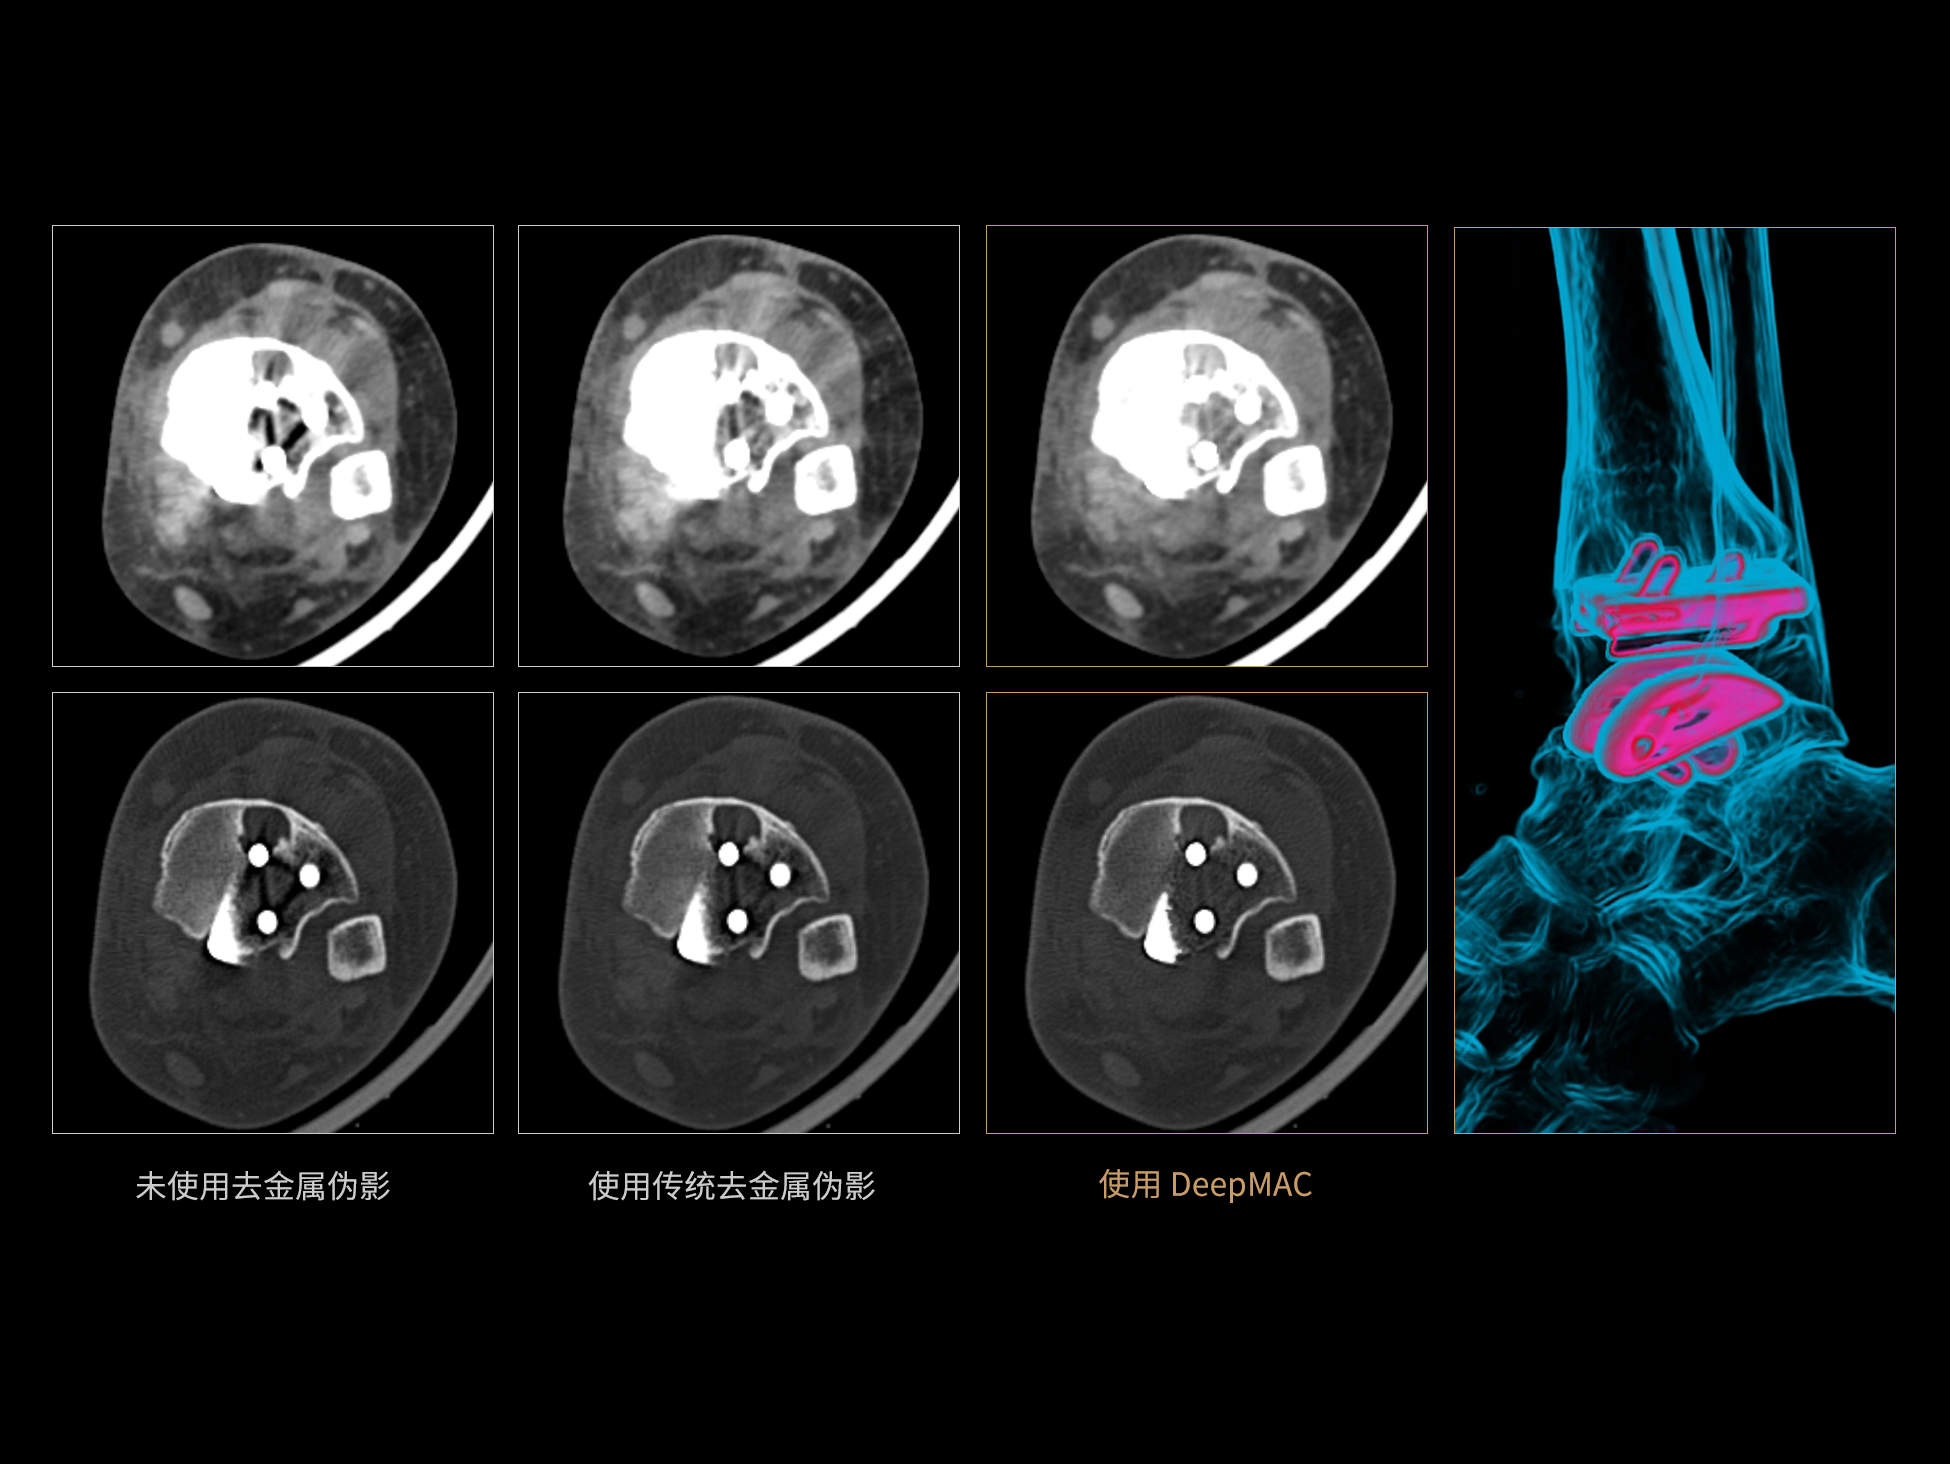

DeepMAC**:AI去金属伪影算法

DeepMAC**智能金属伪影校正技术通过深度学习算法有效解决了临床中各类不规则金属植入物导致的CT成像伪影问题,具备良好的通用性和稳定性。该技术依托大规模、高多样性的训练数据集,覆盖了包括髋关节置换体、脊柱内固定器(胸腰椎/颈椎)、四肢骨科植入物、牙科修复体以及血管介入弹簧圈等在内的金属植入物类型。通过深度神经网络的特征提取与解剖结构重建优化,DeepMAC** 在有效抑制金属伪影的同时,最大程度地保留了真实的解剖细节,显著提升了影像诊断的准确性。